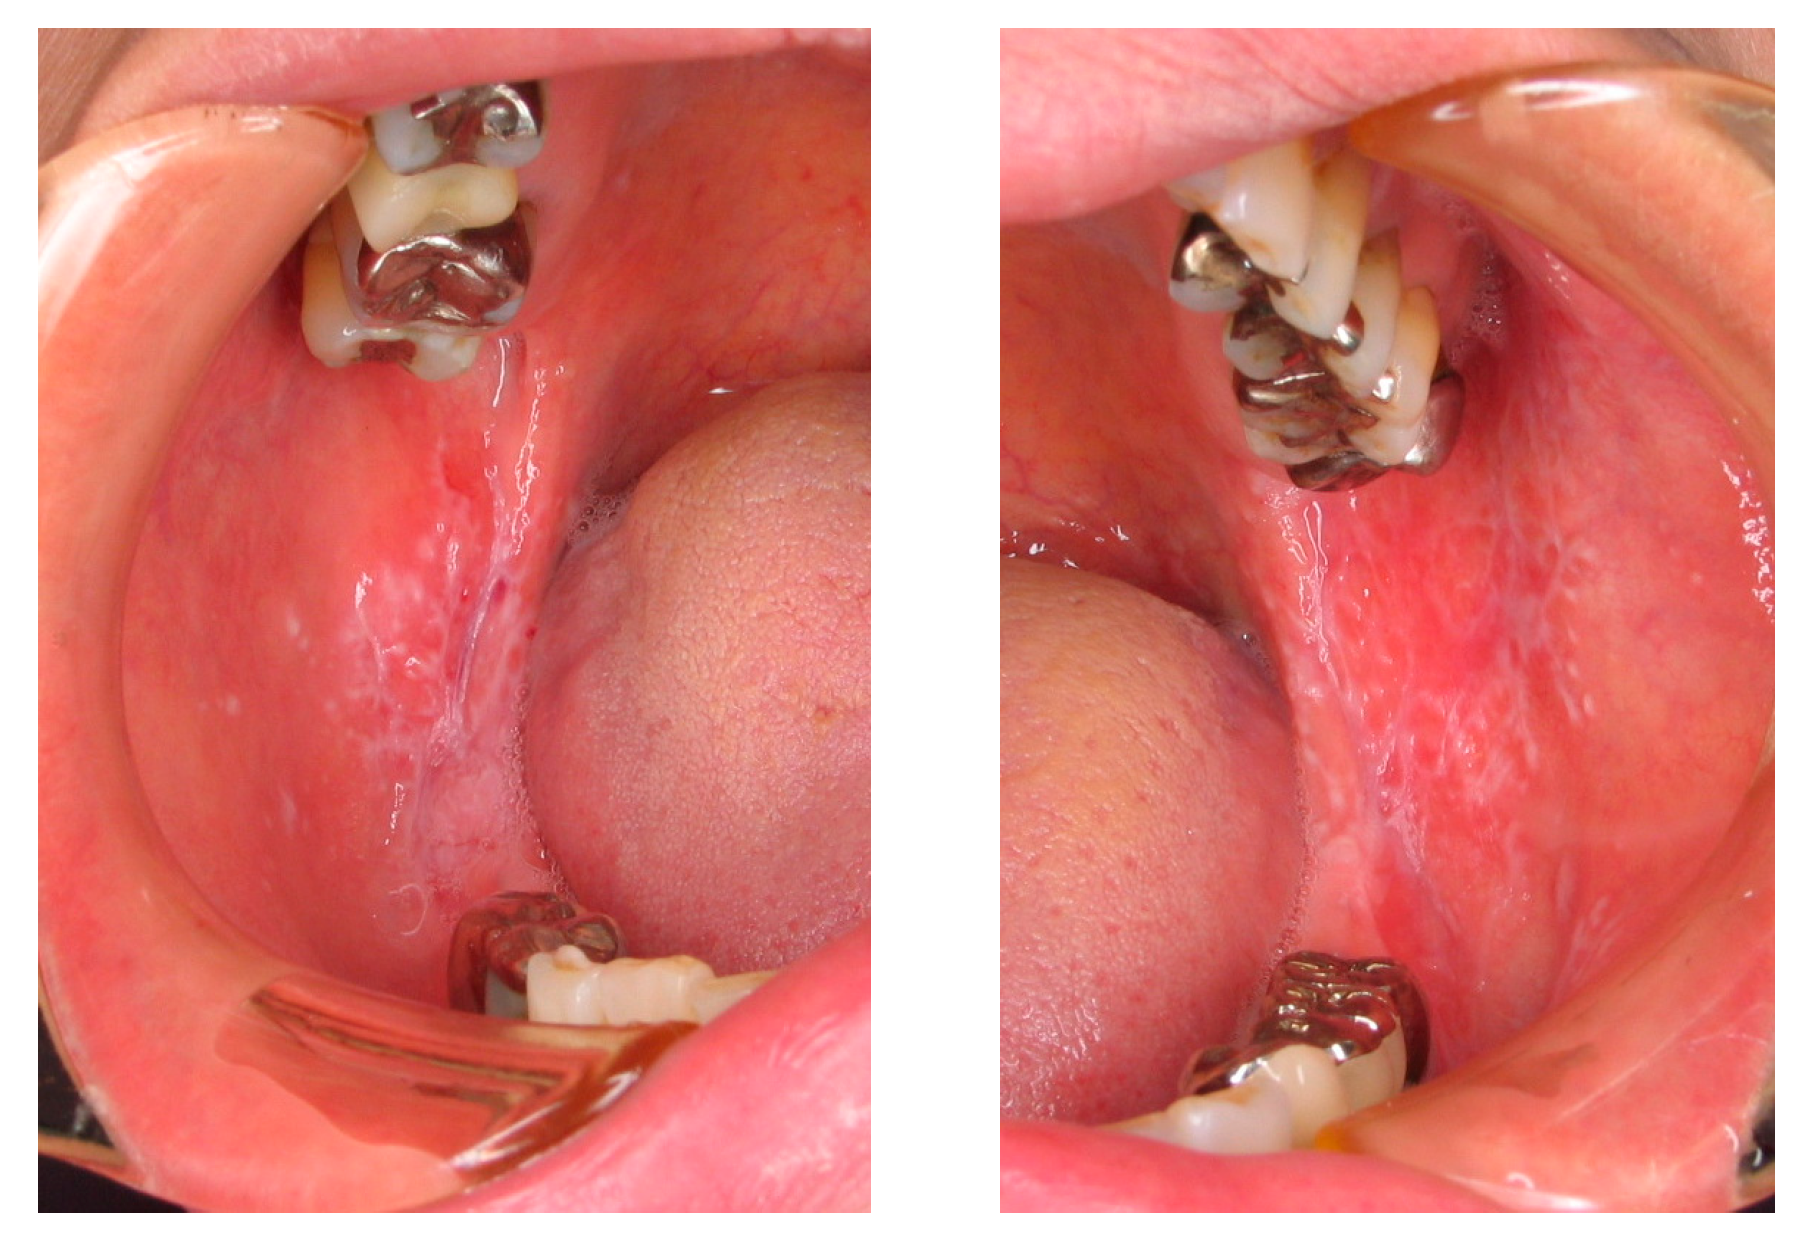

2.2. Oral Lichen Planus (OLP)

3.2.2. OLP